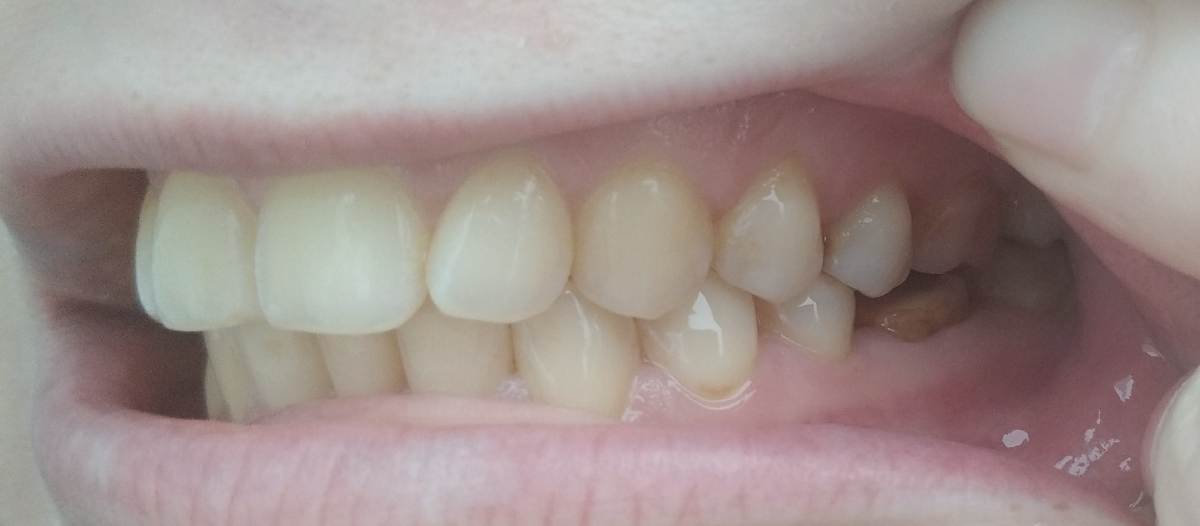

Здравствуйте, подскажите, целесообразно и нужно ли в моем случае ортодонтическое лечение? После лечения зубов планирую установку имплантов в области 36 и 46 зубов. Нужно ли что-то исправлять, или в моем случае можно поставить импланты как есть, без негативных последствий со стороны прикуса? Ортопед на консультации сказал, что можно, по поводу прикуса ничего сказано не было. Была у 2 ортодонтов: первый сказал, что прикус глубокий, и нужно исправлять брекетами. Второй сказал, что небольшие нарушения есть, но как я поняла, не сильно критичные (в области верхних резцов, боковых зубов на верхней челюсти, поэтому наблюдается оголение десны из того, что запомнила), и рекомендовал лечение элайнерами. Жалоб нет, кроме бруксизма (врачи сказали, что причина не в прикусе) и смущает выдвинувшийся 16 зуб. Этот панорамный снимок выдали после КТ, КТ также есть на диске. Спасибо.